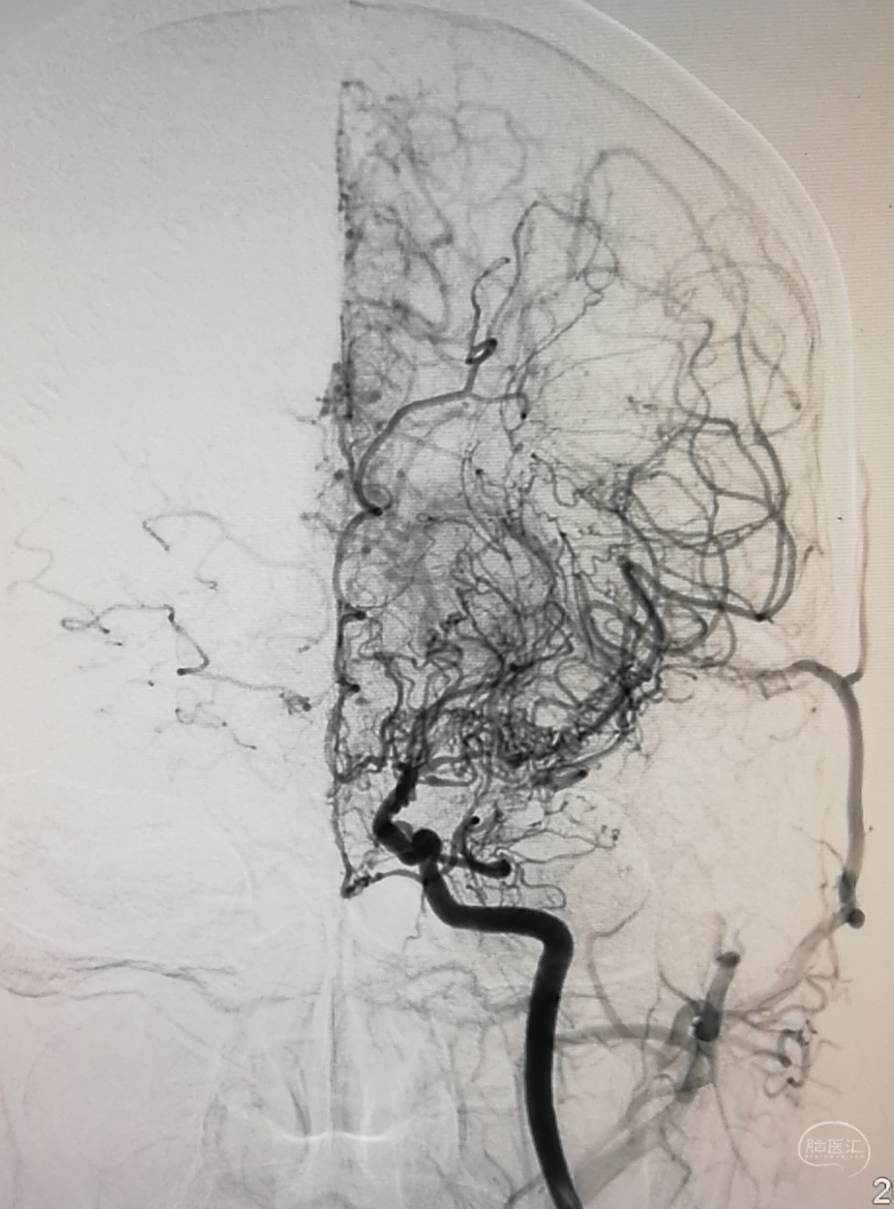

DSA示:左侧大脑中动脉闭塞,烟雾样血管形成。

DSA示颞浅A未向颅内代偿。

DSA示:左侧大脑前、大脑中动脉闭塞,烟雾样血管形成。